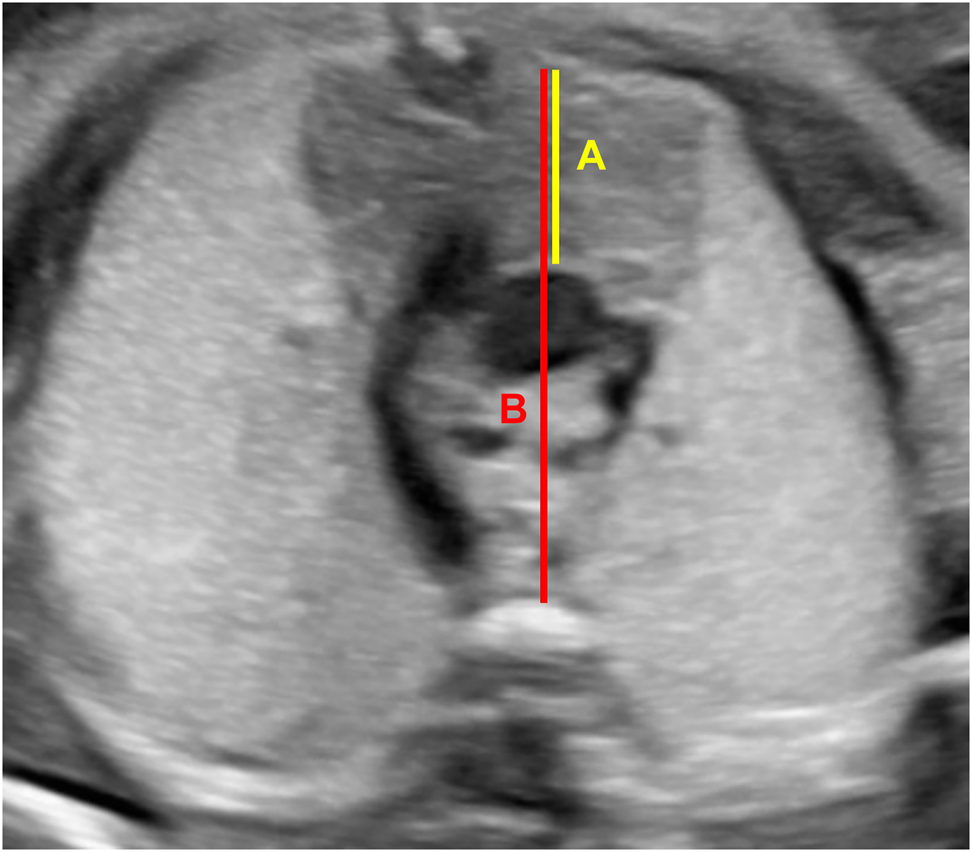

The gestational age of the patients was determined by the last menstrual period or first trimester crown-rump length. The pregnant women who recovered from COVID-19 were called by telephone and evaluated four weeks after the infection was confirmed. Thymus measurements were performed between 28 and 36 weeks of gestation. The same maternal fetal medicine specialists who are experienced for fetal thymic evaluation (SGA, ET) performed USG evaluations with software of GE Voluson E8 Ultrasound machine C 2–9 convex probe (3–9 MHz). To avoid orthostatic hypotension, examinations were performed in a semi-Fowler position. A transversal section of the fetal thorax in the three-vessel view was used for the measurement of the fetal thymus size. The thymus was identified as a homogeneous structure at the level of the three-vessel view, in the anterior mediastinum, in front of the great vessels. The fetal sternum and the fetal spine were defined for an eligible measurement. The thymus diameter (anteroposterior thymus diameter) was measured from the posterior edge of the fetal sternum through the aorta. The thorax diameter (intrathoracic mediastinal diameter) was then measured from the posterior edge of the fetal sternum, through the anterior edge of the fetal vertebra. The thymic-thoracic ratio (TTR) was calculated as follows: thymus diameter/thorax diameter (see Figure 1).

Thymus and thorax diameters. (A) Thymus diameter (anteroposterior thymus diameter) and (B) thorax diameter (intrathoracic mediastinal diameter), TTR: (A)/(B).